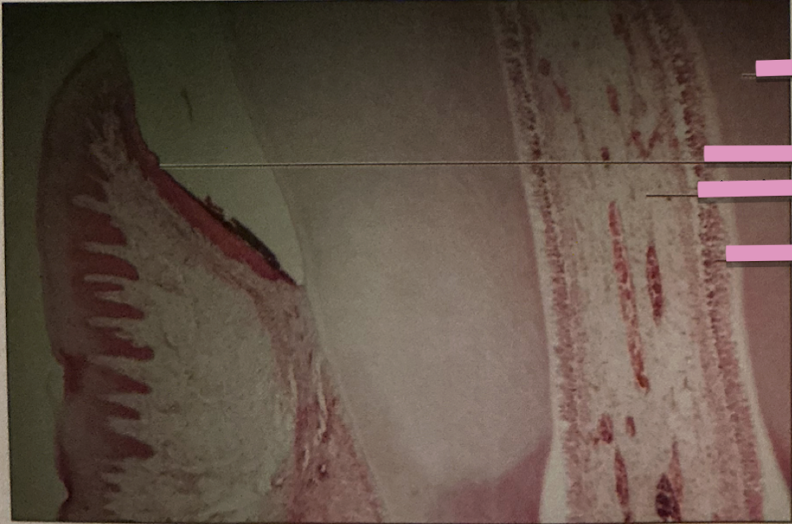

larynx

larynx

cartilaginous structure under epiglottis & has vocal cords

trachea

trachea

windpipe reinforced w/ hyaline cartilage rings —> inhale and exhale

pseudostratified ciliated columnar epithelium

moves mucus along inner laminal surface